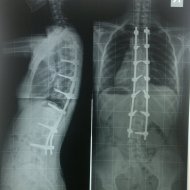

Farklı tipte skolyozu olan hastaların ameliyat öncesi ve sonrası fotoları: